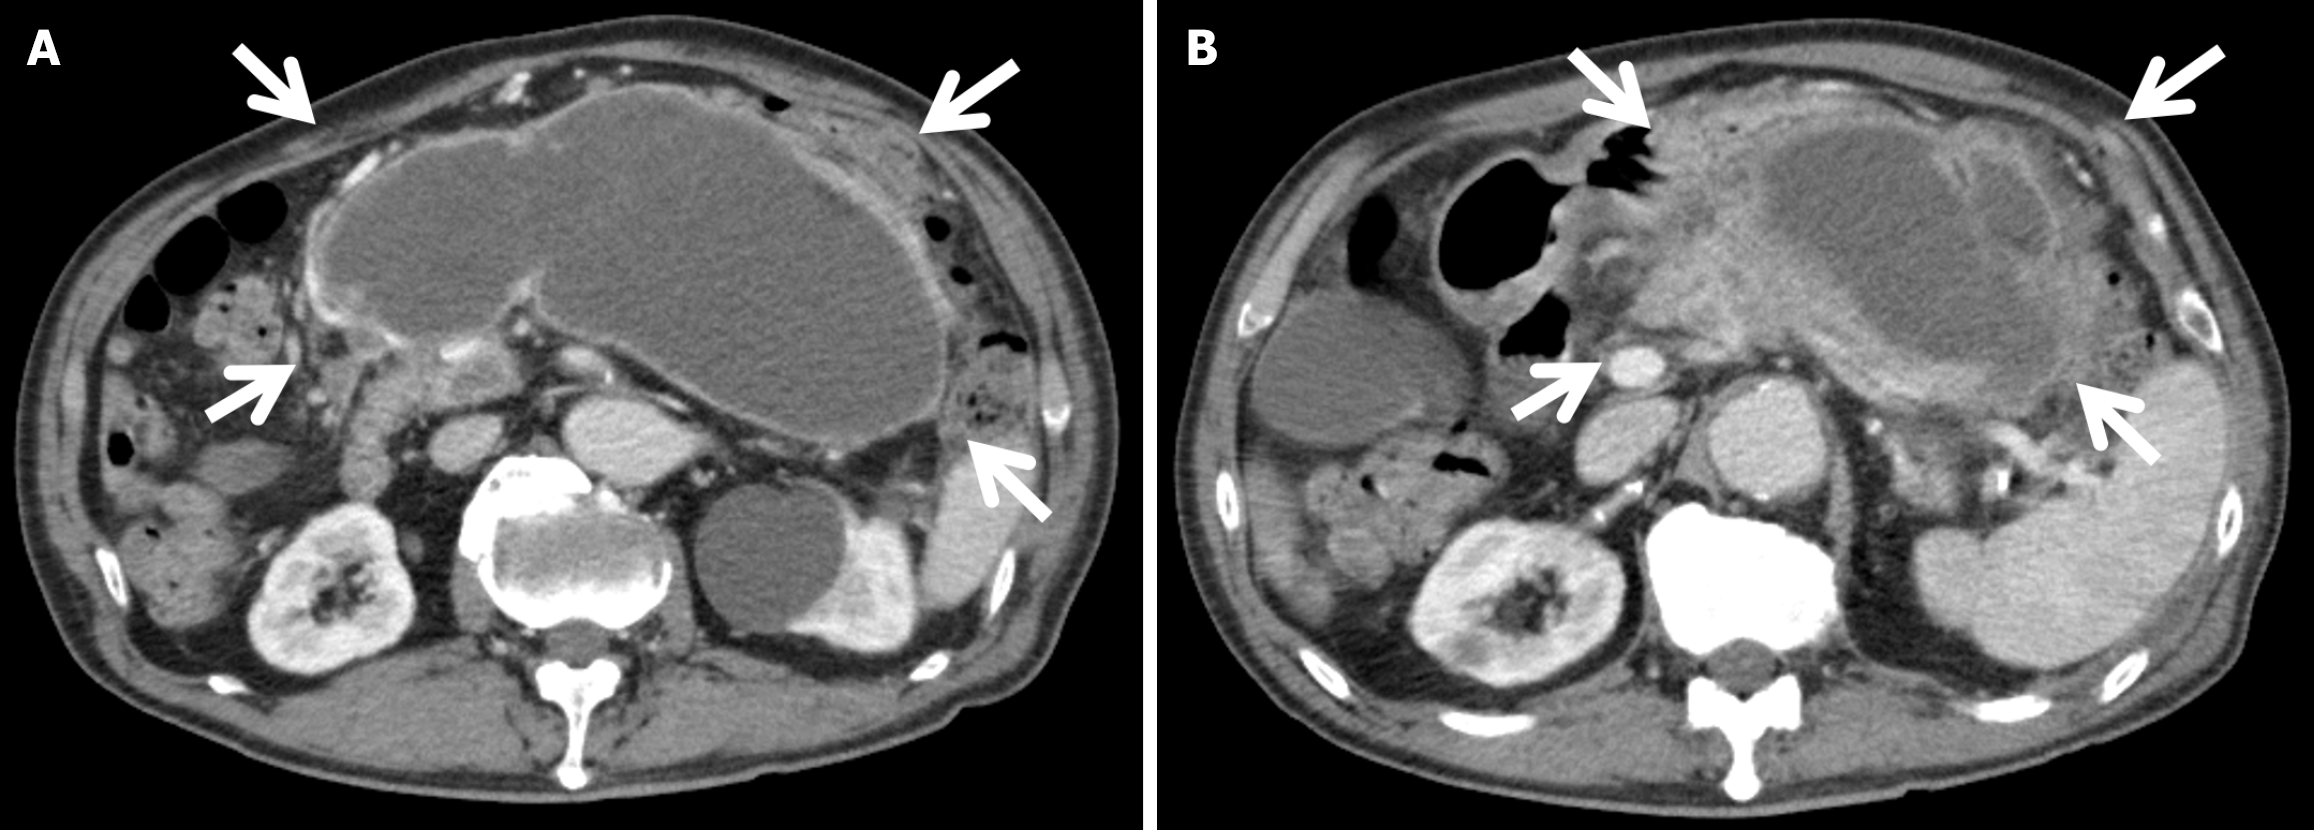

Figure 1 Contrast-enhanced computed tomography on postoperative day 42.

The heterogeneous enhancement and fluid collection (surrounded by white arrows) in the pancreatic body and tail, which were consistent with walled-off necrosis (WON). A: Caudal slice of the WON; B: Cranial slice of the WON.